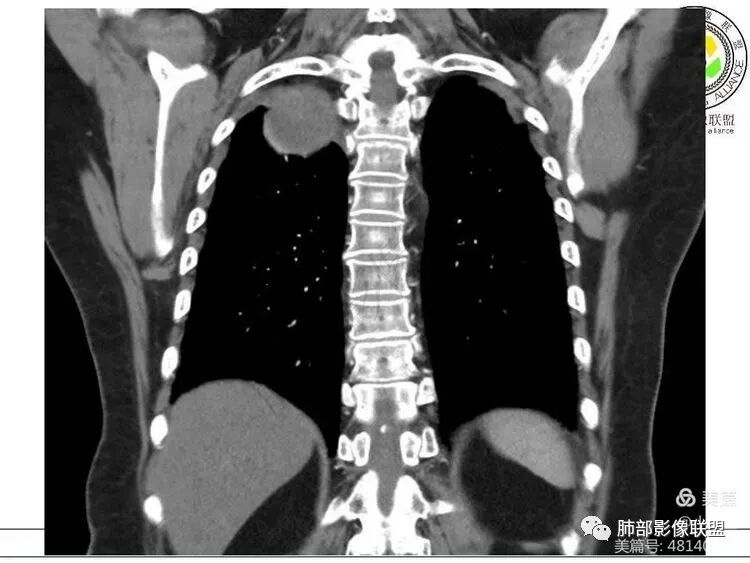

1. 右上胸廓入口区类椭圆形块影,边界清楚光整,纵向“嵌顿”于颈根部及上纵隔,向上推移右锁骨下动静脉,向外下方推移上肺胸膜及肺组织(肺血管、支气管),向前推移上腔静脉,界限清楚。

2. 块影不均匀轻度强化,可见较均匀实性区及液性密度区,未见积气、囊壁样结构、钙化或脂肪密度。可疑部分肋间动脉分支进入。

1.块影定位肺外-上纵隔。块影密度以及强化方式不支持胸腔内甲状腺肿、副节瘤、巨淋巴结增生、支气管囊肿以及畸胎瘤等。

肿块部位、密度以及强化特点聚焦于良性神经鞘瘤及孤立性纤维瘤。

3.而“A/B”区密度特点以及上下径较大更支持神经鞘瘤,尽管这不属于好发部位。